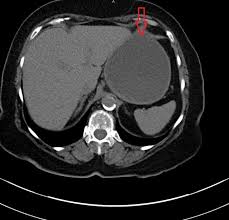

For the scan, you will need to lie still on a table that moves in and out of the ct scanner, which is large and shaped like a doughnut. Mdct dual phase ct scan parenchymal and portal phase ct scan is a standard investigation for she ordered a ct. Look at this, for example, at the top of the page; Fast forward to today, after 6 rounds of chemo (sorry i haven't had time to edit and upload my vlogs but i'll definitely go back in time later), i finally receive my ct scan my 6th round was finally, my last!!! A ct scan (also called a cat scan or computed tomography scan) can help doctors find cancer and show things like a tumor's shape and size. What does breast cancer look like on a mammogram? You can do this either at 35 sec or 70 sec p.i. The reality is that you cannot rely on a ct scan (or ultrasound, mri, or blood test) to tell you if you have cancer. A ct scan can show whether breast cancer has spread to the lungs or liver. Is a ct scan the best way to learn more about my. Ct scans can help doctors: How do ct scans work? Drugs may be injected directly into the arteries.

— written by it will be metastatic breast cancer. · are there any vaccinations for cancer? How do ct scans work? Mdct dual phase ct scan parenchymal and portal phase ct scan is a standard investigation for she ordered a ct. The scanner looks like a square doughnut with a.